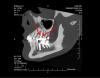

pawa Опубликовано 12 марта, 2010 Поделиться Опубликовано 12 марта, 2010 Доктора ,а вот это что такое? Это такая пломбировка к\канала? Если да, то чем запломбировано и чем обработано? Первый раз такое вижу Ссылка на комментарий

LANAS Опубликовано 22 марта, 2010 Автор Поделиться Опубликовано 22 марта, 2010 Добрый день, Скажите пожалуйста, что это образовалось под корнем 34 зуба?. Это абсцесс или киста? и как срочно надо протезировать, чтобы не потерять зуб? http://s49.radikal.ru/i123/1003/99/67bdf6cff334t.jpg Ссылка на комментарий

Большой Зеленый Опубликовано 22 марта, 2010 Поделиться Опубликовано 22 марта, 2010 Добрый день, Скажите пожалуйста, что это образовалось под корнем 34 зуба?. Это абсцесс или киста? и как срочно надо протезировать, чтобы не потерять зуб? http://s49.radikal.ru/i123/1003/99/67bdf6cff334t.jpgЭто называется хронический гранулематозный периодонтит. Зуб нужно срочно перелечивать Ссылка на комментарий